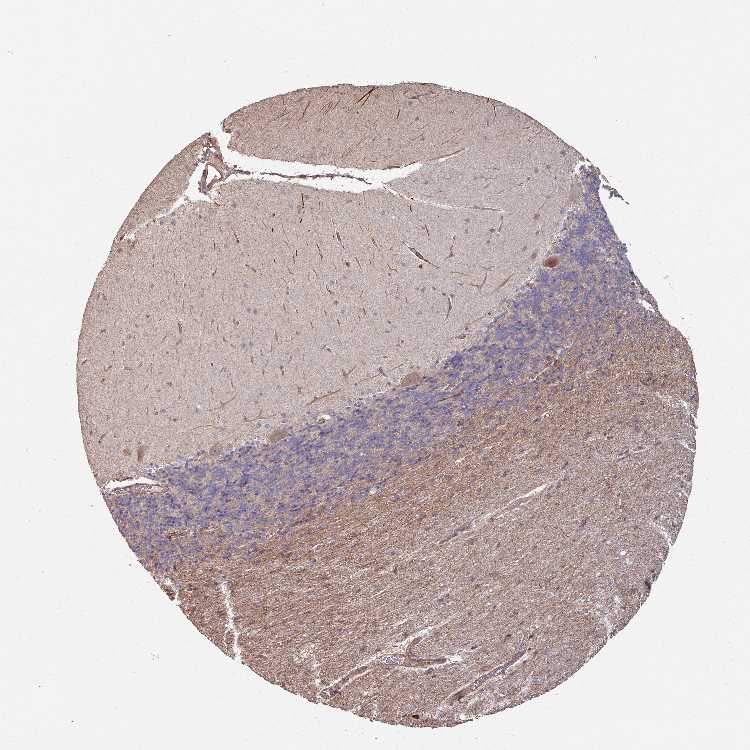

BRAIN CEREBELLUM Show tissue menu

CEREBELLUM - Antibody stainingi

Antibody staining in the annotated cell types in the current human tissue is reported as not detected, low, medium, or high, based on conventional immunohistochemistry profiling in selected tissues. This score is based on the combination of the staining intensity and fraction of stained cells.

Each image is clickable and will lead to virtual microscopy that enables deeper exploration of all samples and also displays staining intensity scores, fraction scores and subcellular localization as well as patient and tissue information for each sample.

Antibody HPA040865Antibody HPA048197

Purkinje cells MediumMedium

Cells in granular layer Not detectedLow

Cells in molecular layer Not detectedNot detected